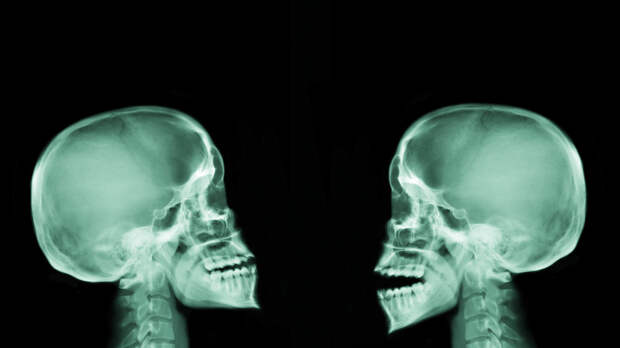

Врач-генетик Кристина Кузнецова рассказала, что ключично-черепной дизостоз считается наследственным заболеванием.

В беседе с «Вечерней Москвой» она заявила, что заболевание затрагивает развитие костей и зубов.

«В результате кости и соединительные ткани, которые должны формироваться у ребёнка, развиваются неправильно.

В основном заболевание влияет на кости свода черепа и ключицы», — пояснила Кузнецова.Как добавила врач, болезнь может спровоцировать стоматологические и ортопедические проблемы и вызвать ряд других осложнений.